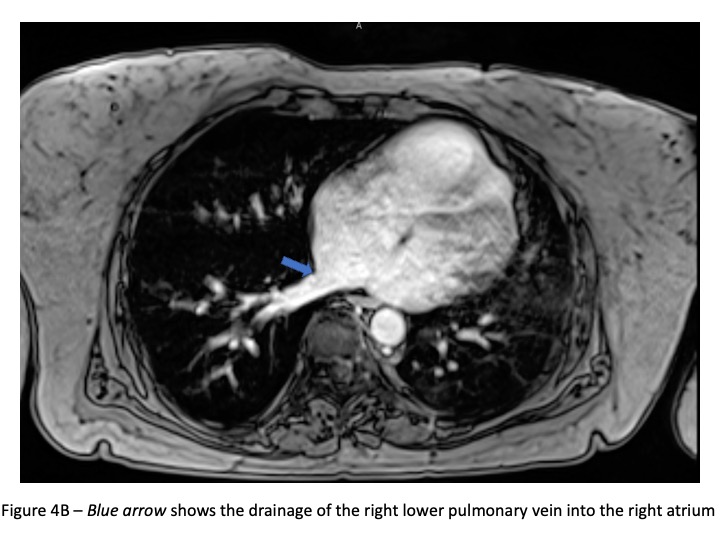

The differential diagnosis of a dilated right heart is broad. The possibilities include Ebstein anomaly, primary pulmonary hypertension, chronic lung disease, arrhythmogenic right ventricular cardiomyopathy, and other congenital heart lesions such as an atrial septal defect or a coronary artery fistula. Though congenital heart disease is less likely in an elderly patient, this should still be considered. The ECG (Figure 3) is non-specific but shows increased right sided voltages and 1st degree heart block. A transthoracic echo showed right heart dilation (Figure 1), but pulmonary vein abnormalities are challenging to ascertain in the setting of sub-optimal echo windows in an elderly patient. A subsequent cardiac MRI confirmed the presence of right heart dilation, and anomalous drainage of the right upper and right lower pulmonary veins into the right atrium (PAPVR) ( Figure 4A-D).

Figure 4B